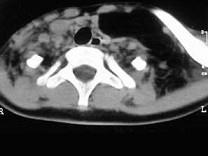

问题 女,17岁,发现左侧颈部包块半年余,PE:病灶质软,境界不清,无压痛,CT如图所示,应诊断为 ( )

选项 A、颈部淋巴管瘤 B、颈部陈旧性血肿 C、颈部畸胎瘤 D、颈部错构瘤 E、颈部脂肪瘤

答案 E